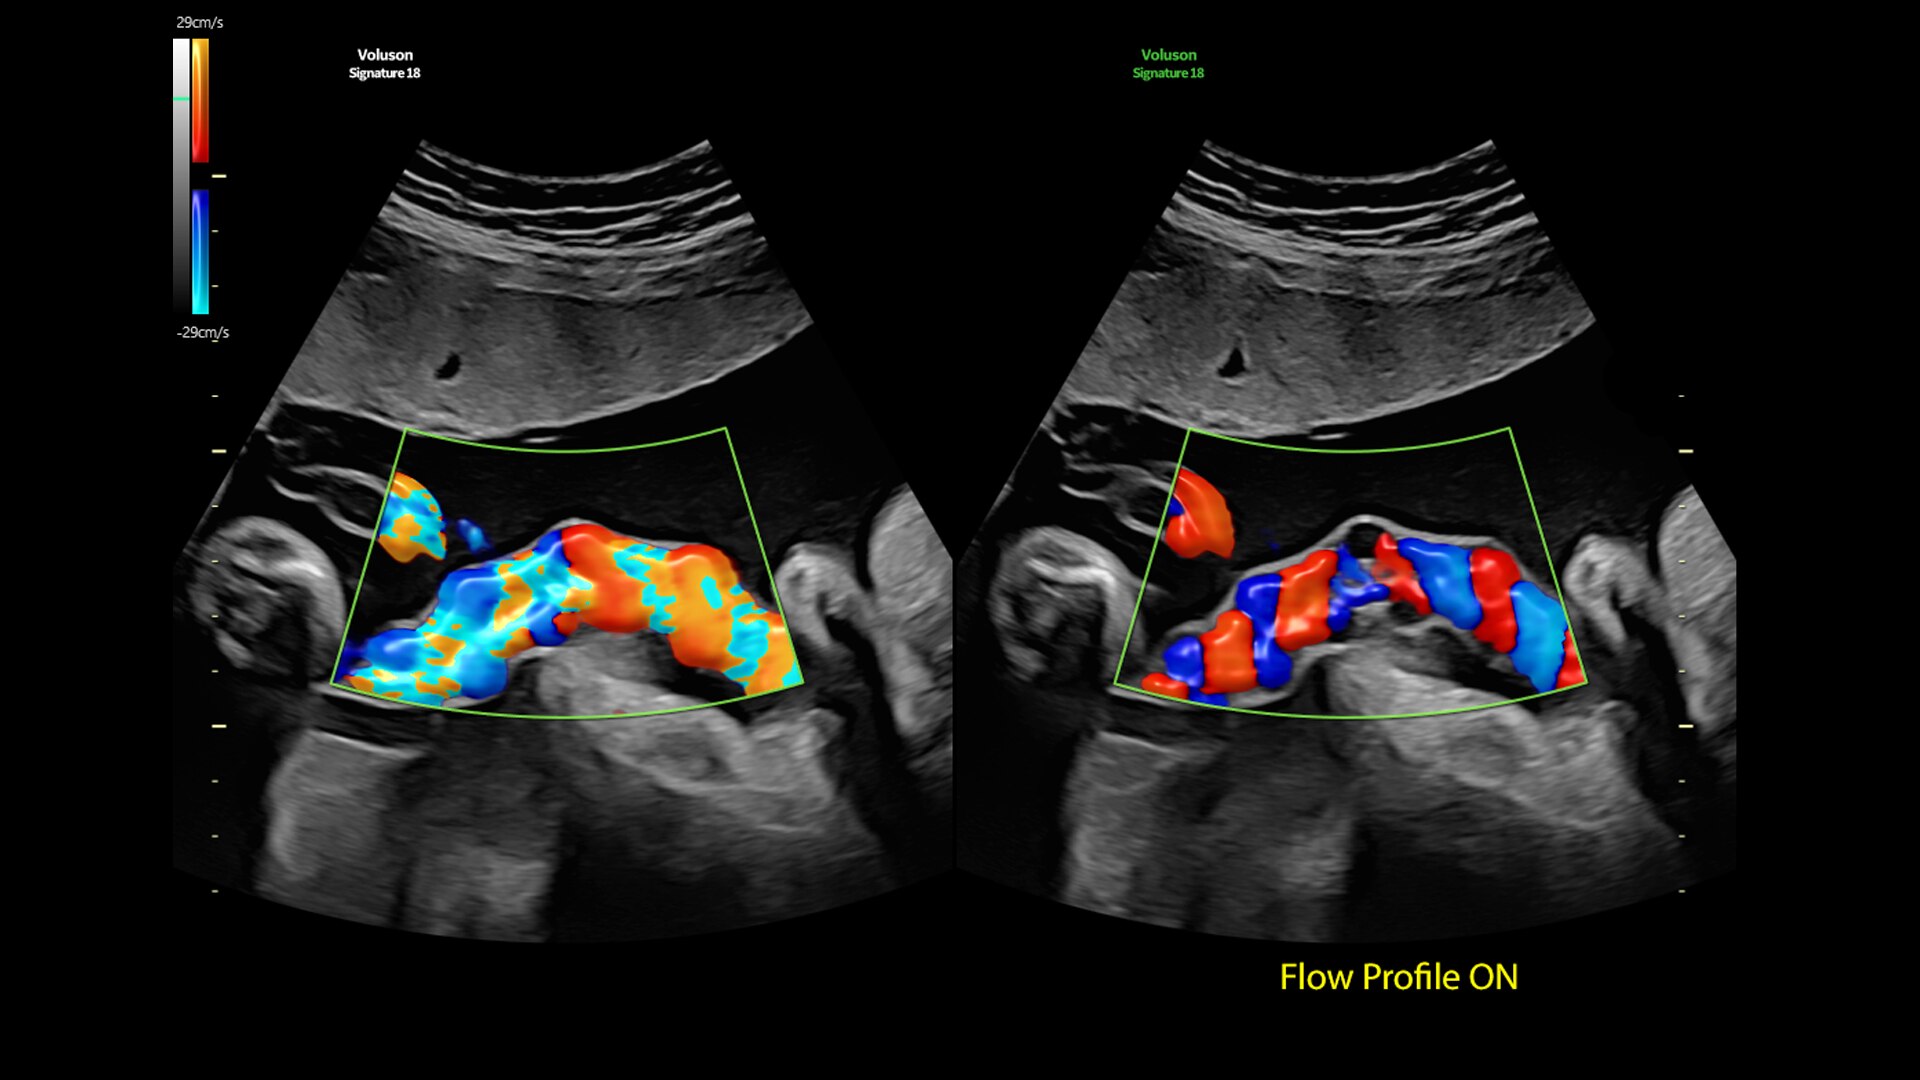

Flow Profiles

Reduce exam time by 56% with Flow Profiles. Dramatically simplifies color and pulsed-wave Doppler optimization by utilizing predefined and optimized settings.